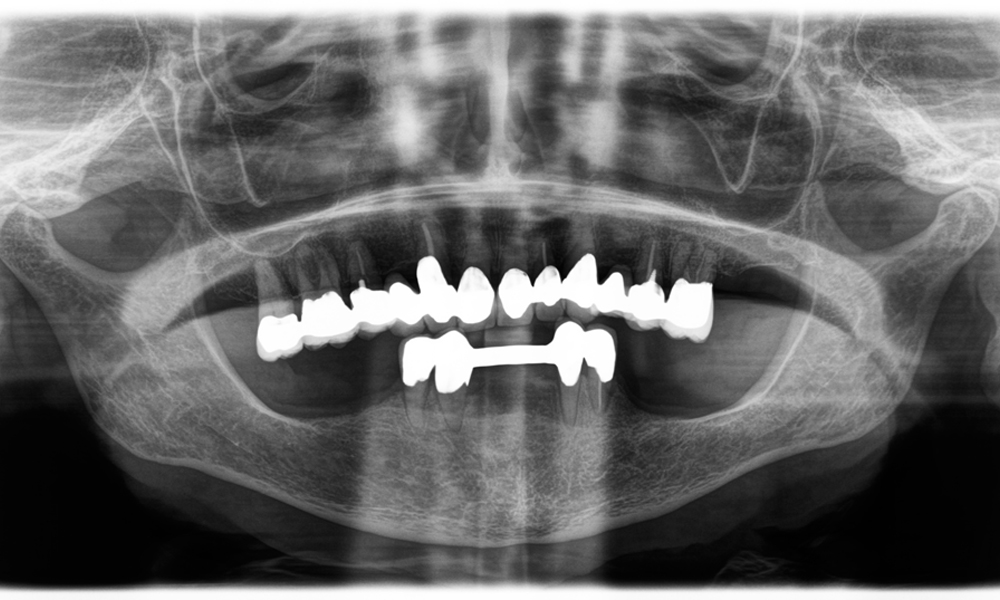

Le Dr Wolfgang Tautschnig, dentiste expérimenté originaire de Salzbourg, a utilisé et évalué le Synea Power Edition pendant plusieurs mois dans divers scénarios cliniques, notamment pour le retrait de couronnes en zircone et le traitement d'alliages de métaux communs. Dans un cas particulier, une patiente de 81 ans s'est présentée pour une amélioration esthétique de ses couronnes PFM (porcelaine fusionnée sur métal) vieilles de 40 ans. Les restaurations existantes ne répondaient plus à ses attentes en termes d'apparence.

Le défi consistait à retirer douze couronnes splintées en alliage métallique sans endommager les dents piliers sous-jacentes. La pièce à main a été utilisée pour sectionner avec précision les couches de céramique et diviser l'armature métallique à l'aide d'une fraise au carbure, ce qui a permis un retrait minimalement traumatisant des couronnes. En seulement 30 minutes, les anciennes restaurations ont été retirées, permettant la préparation d'une nouvelle prothèse, composée de zircone à contour complet dans la région postérieure et de couronnes facettées dans la région antérieure. Le résultat a été une restauration complète qui a permis d'obtenir un succès tant fonctionnel qu'esthétique (voir fig. 1).